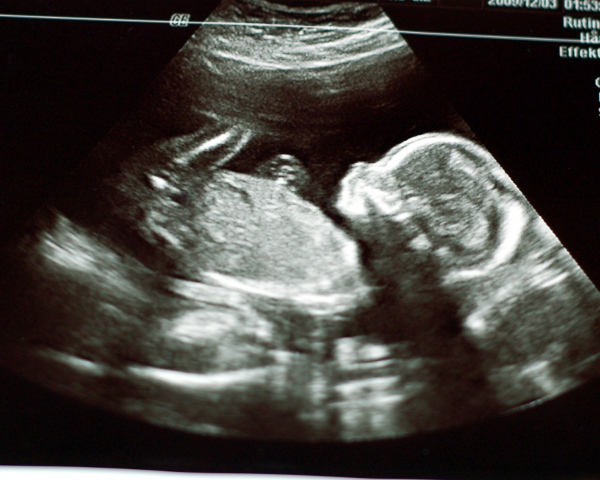

Vi hade varit riktigt snälla i år allihopa och tomten kom med fantastiska paket. Julmaten smakade riktigt gott och det var med dyster min jag insåg att jag inte skulle få i mig så mycket som jag önskat. Bebis tar upp mer och mer plats i magen för var dag som går och det hela känns mer verkligt än någonsin. Bilder säger mer än ord så här kommer lite bilder från vår jul.